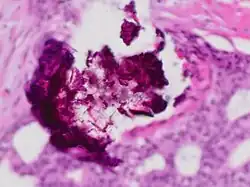

Calcium phosphate is the usual constitution of microcalcifications of the breast, particularly dystrophic calcifications. Microcalcifications as can be seen on mammography can be an early sign of breast cancer. Based on morphology, it is possible to classify by radiography how likely microcalcifications are to indicate cancer.[7]

Histopathology of dystrophic calcium phosphate microcalcifications in ductal carcinoma in situ (DCIS) of the breast, H&E stain.